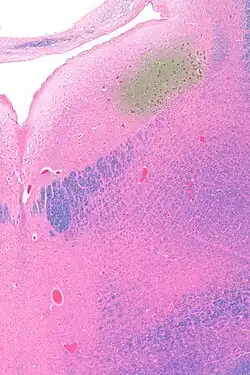

The locus coeruleus (/sɪˈruːliəs/) (LC), also spelled locus caeruleus or locus ceruleus,[1] is a nucleus in the pons of the brainstem involved with physiological responses to stress and panic.[2] It is a part of the reticular activating system in the reticular formation.[3]

Anatomy

The locus coeruleus (LC) is located in the posterior area of the rostral pons in the lateral floor of the fourth ventricle. It is composed of mostly medium-size neurons. Melanin granules inside the neurons contribute to its blue colour. Thus, it is also known as the blue nucleus, or the nucleus pigmentosus pontis (heavily pigmented pontine nucleus).[5] The neuromelanin is formed by the polymerization of norepinephrine and is analogous to the black dopamine-based neuromelanin in the substantia nigra.

In adult human males,[a] the locus coeruleus has 22,000 to 51,000 total pigmented neurons that range in volume from 31,000 to 60,000 μm3.[6]

The locus coeruleus is affected in many forms of neurodegenerative diseases: genetic and idiopathic Parkinson's disease, progressive supranuclear palsy, Pick's disease, and Alzheimer's disease. It is also affected in Down syndrome.[29] For example, there is up to 80% loss of locus coeruleus neurons in Alzheimer's disease,[30] Mouse models of Alzheimer's disease show accelerated progression after chemical destruction of the locus coeruleus.[31] Neurofibrillary tangles, a primary biomarker of Alzheimer's disease, may be found in the locus coeruleus decades before any clinical symptoms.[32] The norepinephrine from locus coeruleus cells in addition to its neurotransmitter role locally diffuses from "varicosities". As such it provides an endogenous anti-inflammatory agent in the microenvironment around the neurons, glial cells, and blood vessels in the neocortex and hippocampus.[18] It has been shown that norepinephrine stimulates mouse microglia to suppress Aβ-induced production of cytokines and promotes phagocytosis of Aβ.[18] This suggests that degeneration of the locus coeruleus might be responsible for increased Aβ deposition in AD brains.[18] Degeneration of pigmented neurons in this region in Alzheimer's and Parkinson's disease can be visualized in vivo with Neuromelanin MRI.[33] Since the marked degeneration of locus coeruleus, and the neuroprotective properties of noradrenaline, Ian Robertson proposed the "Noradrenergic Theory of Cognitive Reserve" [34] which postulates that the upregulation of the locus coeruleus-noradrenergic system throughout the lifespan may enhance cognitive stimulation contributing to cognitive reserve preventing from neurodegeneration. Evidence appear to support this theory reporting the locus coeruleus integrity primarily responsible of biological brain maintenance,[35][36][37] including brain clearance,[38] cognitive efficiency, and reduced neuropathological burden.[35][39][40][41]